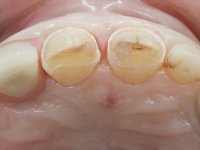

Paciente do sexo feminino, com 47 anos não fumadora. Apresentou-se na consulta com o dente 1.3 com tratamento endodôntico e com um espigão falso coto fundido, reabilitado com uma coroa provisória. Os dois incisivos laterais superiores são conoides e de reduzida dimensão. O dente 2.2 apresenta mobilidade, consentânea com uma significativa reabsorção óssea entre o dente 2.1 e o dente 2.3 Os dois incisivos centrais estão separados por um diastema de 3mm e o dente 2.3 apresenta uma oclusão cruzada com o dente antagonista. Verifica-se também a ausência de alguns dentes posteriores e uma higiene oral razoável. Na segunda intervenção realizada passados 8 anos, verificou-se que os incisivos centrais superiores se apresentavam cromaticamente mais escuros e apresentavam um sulco longitudinal no esmalte que estando pigmentado comprometia esteticamente o sorriso. O trabalho realizado na primeira fase do tratamento mostrava-se competente estética e funcionalmente. Por fim, um ano após a última intervenção, a paciente apresentou-se com uma fratura da faceta colocada no dente 2.1 provavelmente em resultado de estar em contacto com o coto do implante. A rigidez da anquilose implantar, pode ter sido a causa desta fratura. Outros casos deste tipo de fratura já foram observados por mim em situações clínicas idênticas. A faceta do dente 1.2 apresentava-se esteticamente comprometida e a própria estrutura dentária apresentava uma pequena cárie e, pelo que se recomendaria a sua substituição.

Oito anos depois, na segunda intervenção, foi proposto o seguinte tratamento:

• Reabitação dos dentes Incisivos Centrais Superiores com facetas de cerâmica feldspática.